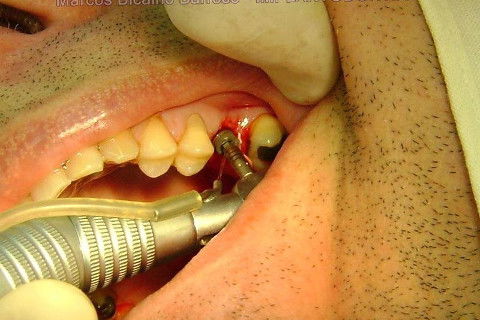

Instalação de um implante em região do 26. Utilizamos um implante cone morse Alvim Neodent 4.3 X 11,5. Foi uma cirurgia muito rápída e minimamente traumática, sem retalho e sutura.